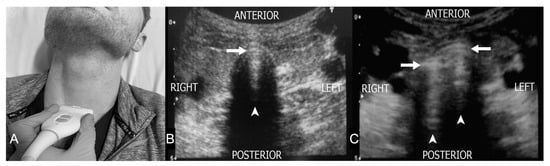

4.1. Suprahyoid View

4.2. Thyrohyoid View

4.5. Suprasternal View